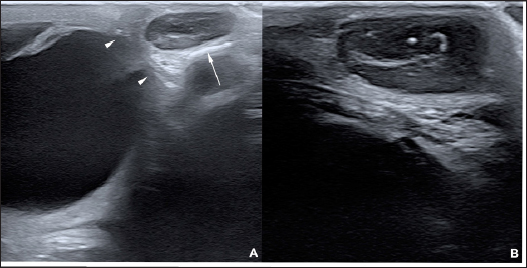

On ultrasound examination, a roughly ovoid (18 × 17 × 9 mm) delineated subcutaneous mass was visible immediately caudal to the lateral angle of the left eye, superficial to the zygomatic arch. This mass was of intermediate and heterogenous echogenicity with a hypoechoic center circumscribed by thin concentric hyperechoic lines (Fig. 3). No bone lesion nor adhesion between the mass and the osseous surface was identified. The left eye was within normal limits. The parotid gland and parotid lymph nodes had a physiological position and a normal ultrasonographic appearance.

Fig. 3. Ultrasonographic images obtained in Case 2 in a longitudinal (temporo-nasal) orientation. The temporal side is on the right of each image. (A) General view showing the relationship with the globe (white arrowheads) and the zygomatic arch (white arrow). (B) Close-up view showing the described architecture and echogenicity.